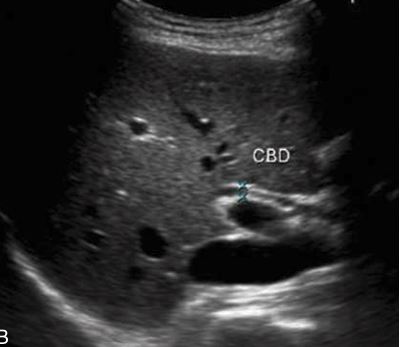

CBD

hartmann’s pouch

Small echogenic Adenoma in GB

what plane is this and what is it showing

SAG - CBD

Distension (hydrops) of the gallbladder but showing what?

sludge with hydrops